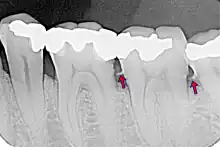

Le tartre peut se déposer sur toute la surface des dents. On distingue :

- le tartre supra-gingival : c'est celui qu'on peut voir à l'œil nu. Il est généralement de couleur blanchâtre ;

- le tartre sous-gingival : c'est le tartre qui s'est déposé sur la racine de la dent, à l'abri de la gencive, au niveau des poches parodontales. Il est souvent beaucoup plus foncé. Ce tartre est le plus dommageable : les bactéries sont protégées à l'intérieur de la poche, et progressivement la flore aérobie se transforme en flore anaérobie, plus pathogène. Par ailleurs, comme on ne le voit pas, on ne s'en rend pas compte.